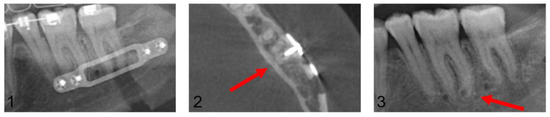

A follow-up of patients with confirmed dental root injuries was conducted at 13 months (median 9.9, min. 6.1, max. 45.5). During this period, none of the injured teeth showed evidence of periapical alterations and no endodontic treatments were performed. Figure 8 presents a case with CT-confirmed dental root injury directly, post-operatively, and after removal of the osteosynthesis material 10.8 months after primary surgery.

Figure 8.

Image (1): Projection of an osteosynthesis screw in the distal root of tooth 36 in the post-operative orthopantomogram after mandibular sagittal osteotomy. Image (2): CT confirmed dental root injury of the distal root of tooth 36 (red arrow). Image (3): Left posterior mandibular region after removal of the osteosynthesis material 10.8 months after primary surgery. The red arrow marks the area of radiologically proven root injury. No apical alterations are shown, and no endodontic treatment had been necessary up to this point.